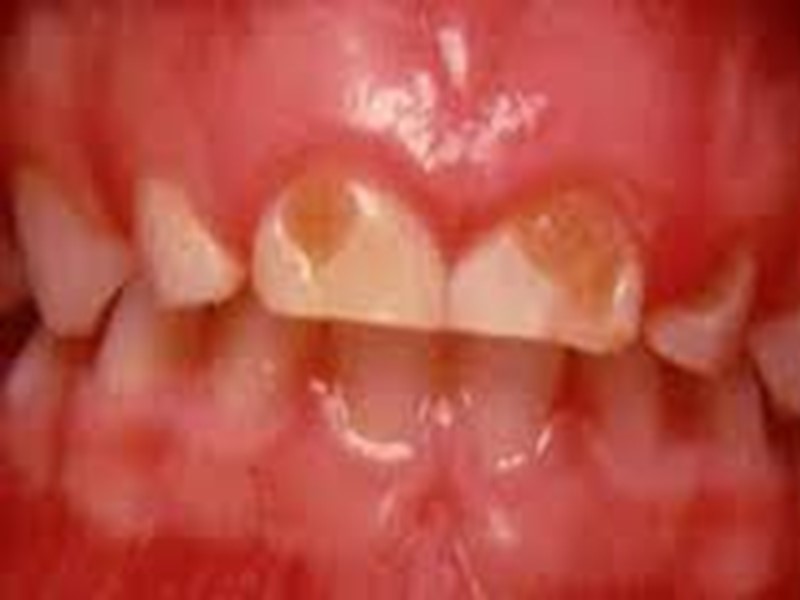

Поверхностный кариес (caries superficialis). жалобы на кратковременную боль от химических раздражителей (сладкого, соленого, кислого) температурные раздражители редко вызывают боль может протекать бессимптомно.

Поверхностный кариес (caries superficialis). При объективном исследовании обнаруживается кариозная полость в пределах эмали с неровными шероховатыми стенками и дном. Зондирование дефекта эмали может быть болезненно, зонд погружается в размягченную эмаль на незначительную глубину. Пульпа зуба при поверхностном кариесе реагирует на ток силой 2— 6 мкА.